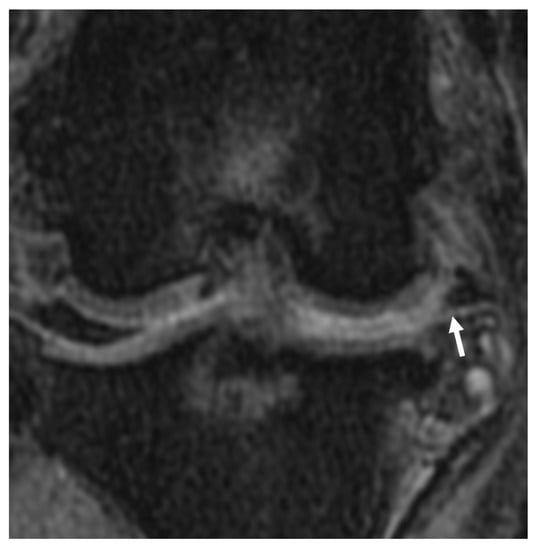

3.2.5. Meniscal and Cartilage Lesions